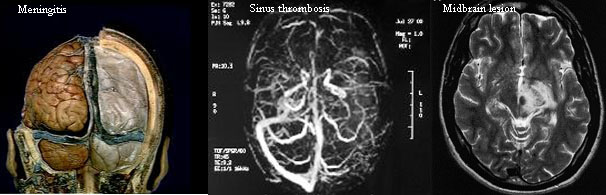

Auto-immune diseases affecting cognition are not rare in neuropsychology however, Neuro-Behcets certainly is! So when it arrived on my doorstep I had to share. What Is Neuro-Behcets (pronounced “Beh- shet”)? It is a chronic multi-system relapsing inflammatory disorder resulting in ulcers in the mouth, genitals, appendages, stomach and intestines. When it manifests in the brain it affects the brain stem, the meninges, cortical and sub-cortical pathways, and other brain structures. There are two types of Neuro-Behcets (NBD), Parenchymal (affecting brainstem, spinal cord, cerebral hemispheres) and non-parenchymal (causing intracranial hypertension, aseptic meningitis, cranial neuropathy and cerebrovascular disorders including aneurysms, vasculitis and occlusions). It is the most dangerous manifestation of Behcets disease and can affect or ‘attack’ cortical as well as subcortical structures in the brain.